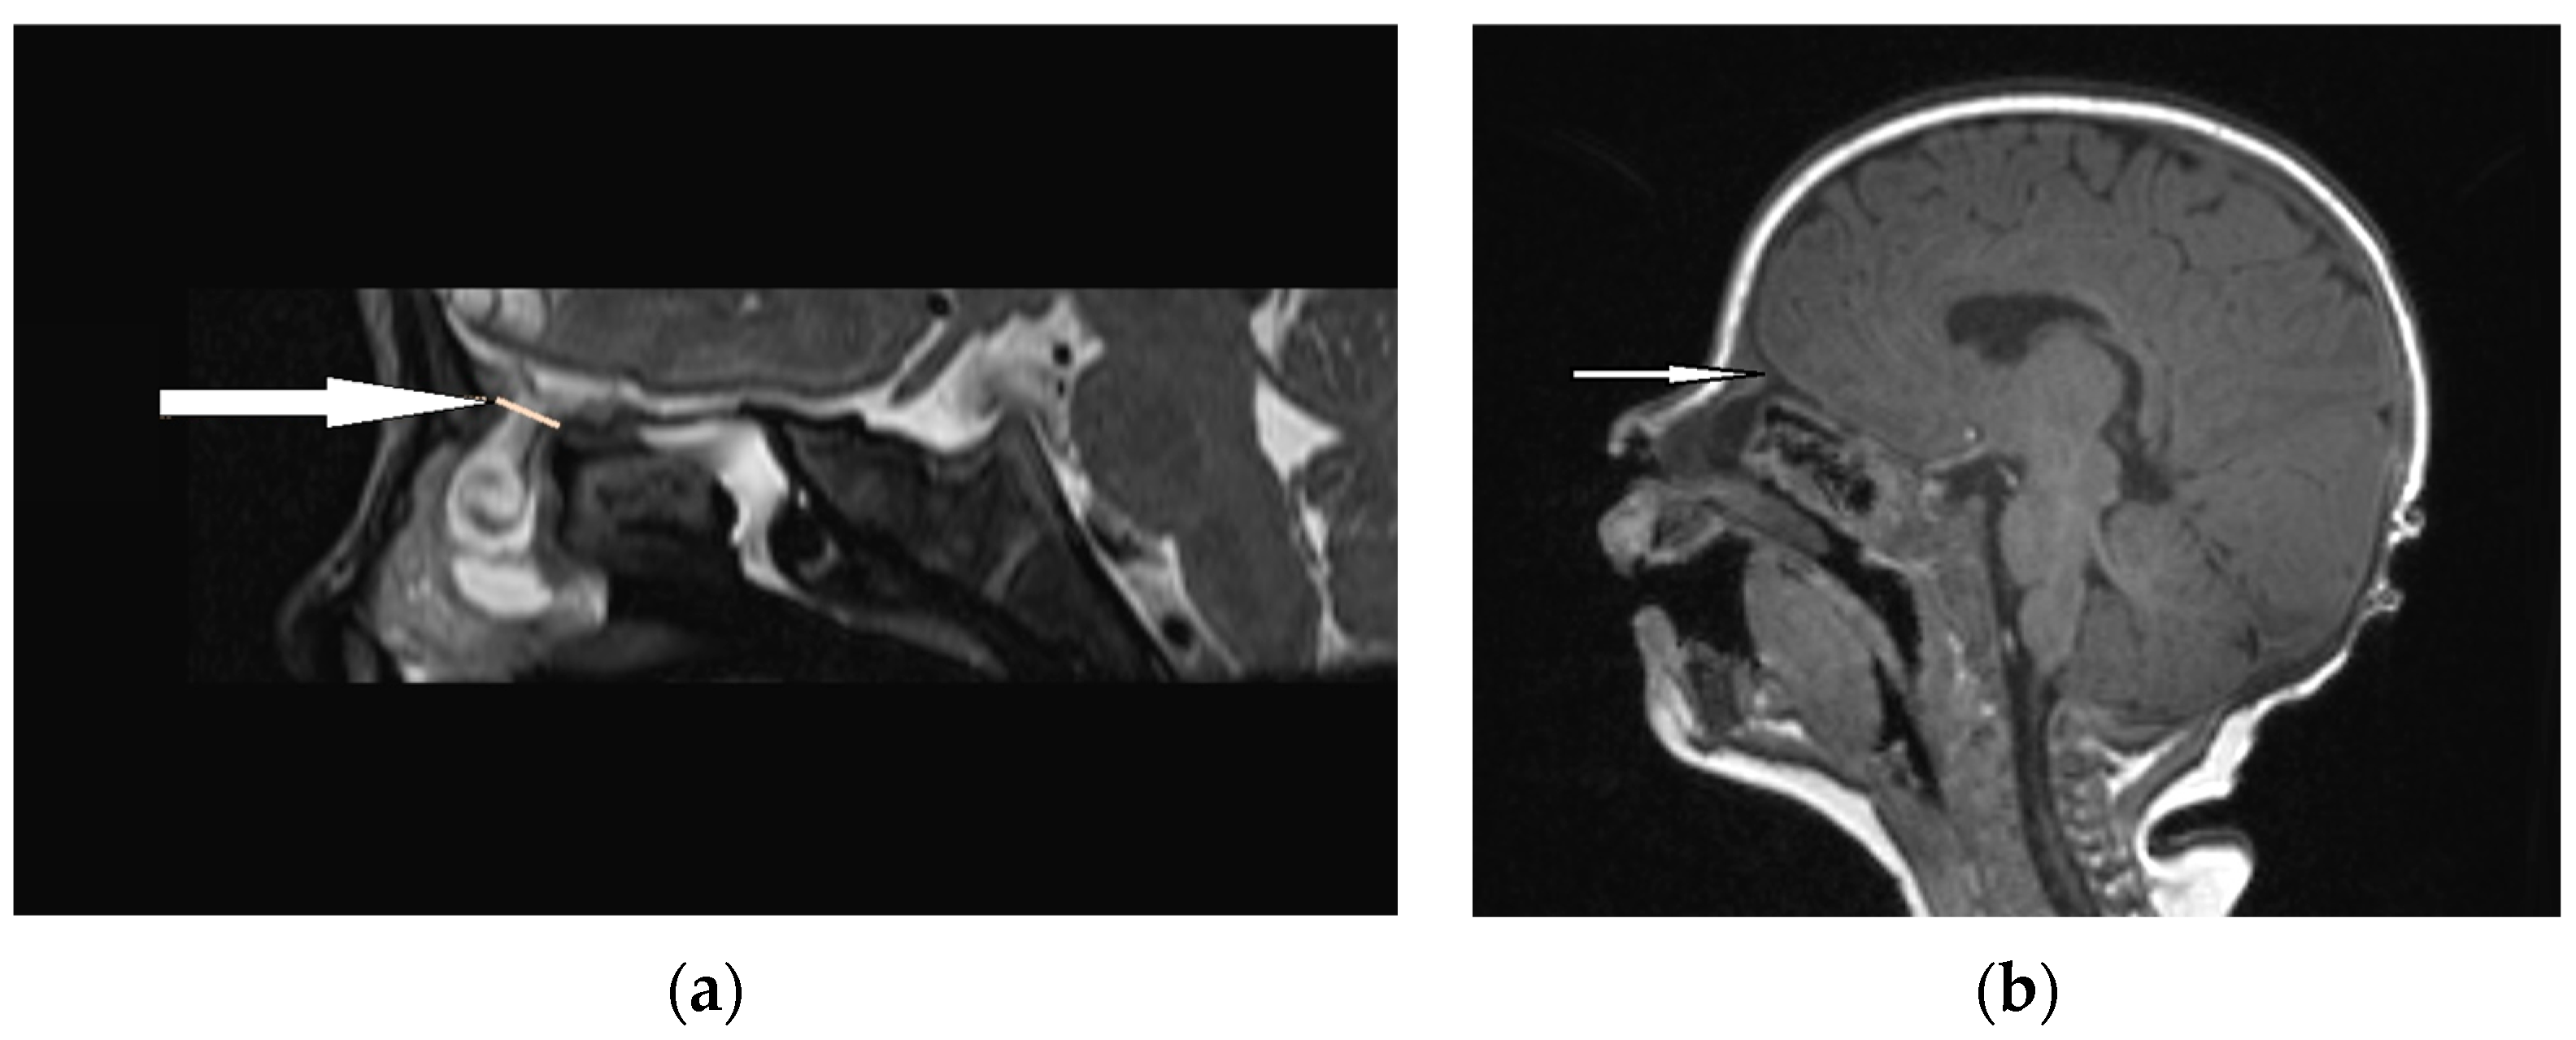

| MRI | Variable signal intensity depending on the protein content; fat-suppressed T1-weighted images—differentiation between skull base defects and enhancing non-ossified cartilage of anterior cranial fossa; DWI—typically high-signal-intensity lesion with corresponding low signal intensity on ADC maps | Discontinuity with the brain parenchyma; variable visualization of a fibrous stalk connection to CNS; well-circumscribed, rounded, or polypoid mass—isointense or rarely hypointense to gray matter on T1-weighted imaging; neural tissue—more hyperintense on T2-weighted images to normal brain parenchyma in most cases; dysplastic tissue usually corresponds with no enhancement or moderate enhancement; noticeable enhancement at the lesion periphery | Herniation of intracranial tissue and its continuity with the brain | |